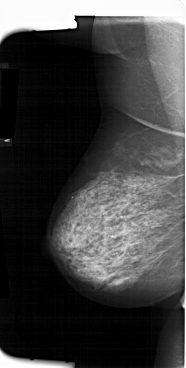

A_1384_1.LEFT_MLO

LEFT_CC LINES 5701 PIXELS_PER_LINE 3211 BITS_PER_PIXEL 12 RESOLUTION 43.5 NON_OVERLAY

LEFT_MLO LINES 6616 PIXELS_PER_LINE 3331 BITS_PER_PIXEL 12 RESOLUTION 43.5 NON_OVERLAY